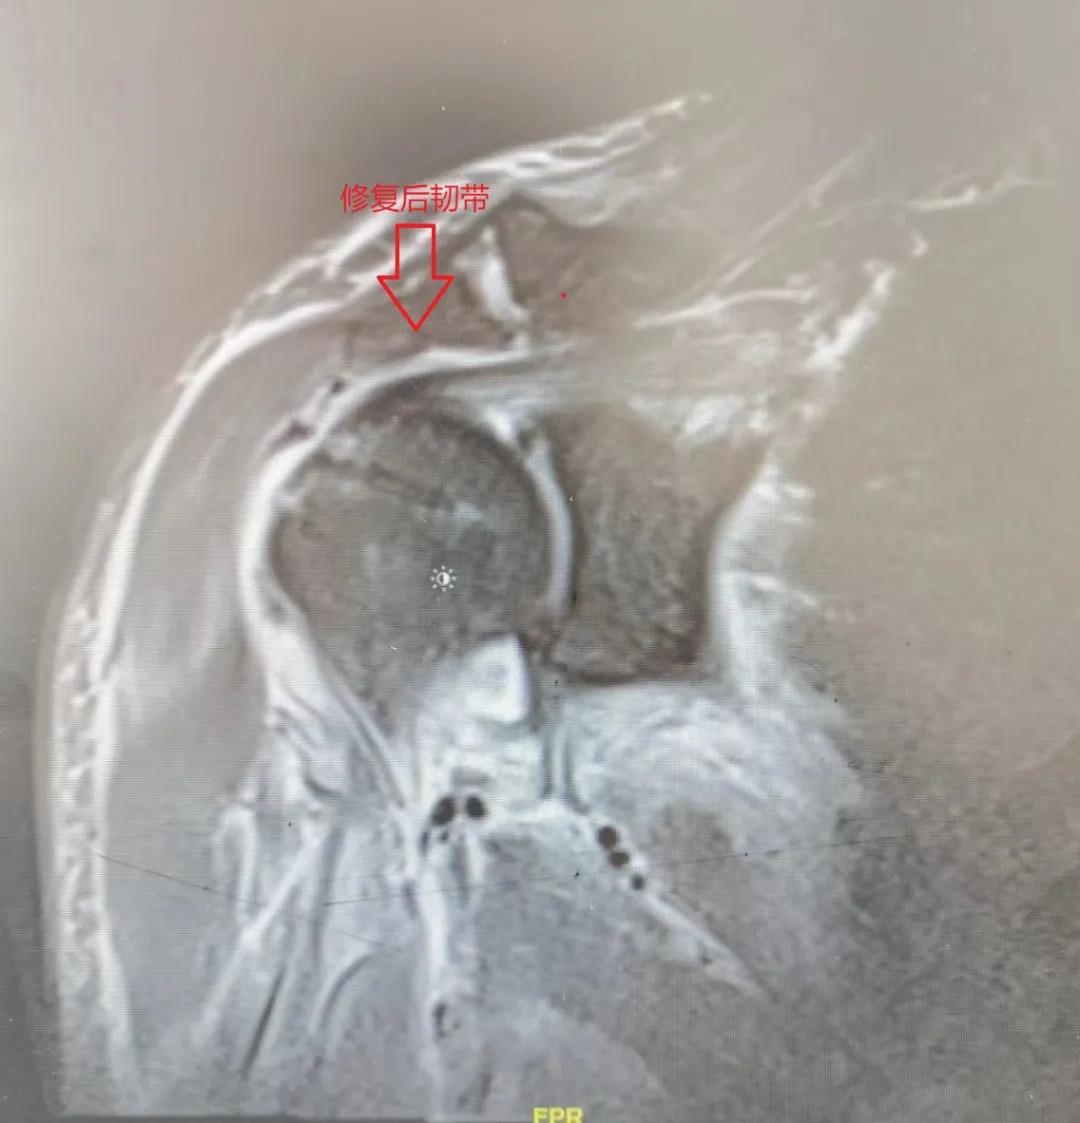

郝亮博士团队在关节镜下行手术治疗,手术仅用时30分钟,就解决了困扰周先生的疼痛。术后患者肩关节处仅仅只有3个不到半厘米的小伤口,第二天就可以开始功能恢复锻炼了。

患者术后复查MRI